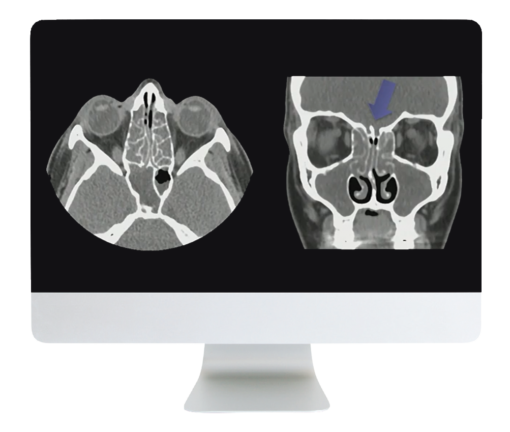

ARRS Cranial Nerve Imaging: From the Least to the Last 2022 Cranial nerve imaging can be a daunting task due to the small nature of the nerves themselves and their complex pathways in the brain and skull base. This course will provide a comprehensive review of the anatomy and pathologies involving the cranial nerves and help to reinforce and revise the participants’ knowledge of this topic.